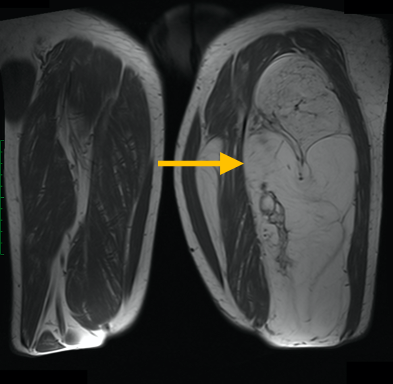

Radiographic imaging is used to help form a diagnosis of liposarcoma. These include X-Ray, MRI, CT and Bone Scans.

An example of an MRI is shown.